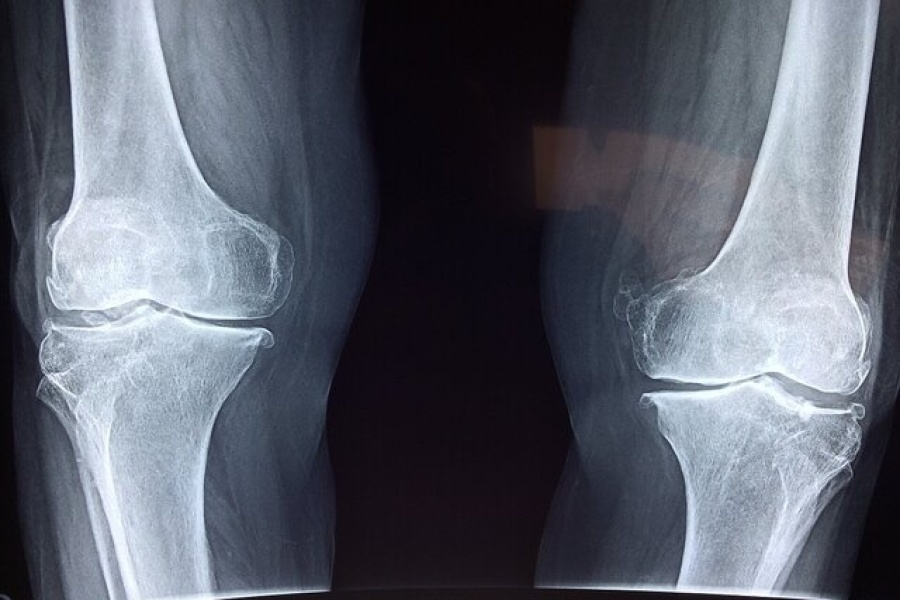

فوق تخصص بیماری‌های روماتولوژی با اشاره به اهمیت پیشگیری و تشخیص زودهنگام پوکی استخوان گفت: این بیماری به کاهش مواد معدنی و آلی در بافت استخوان گفته می‌شود و متأسفانه اصلی‌ترین علامت آن، بی‌علامتی است؛ یعنی در بسیاری از موارد بیمار هیچ نشانه‌ای ندارد و استخوان‌ها به‌تدریج و بی‌صدا دچار ضعف و پوکی می‌شوند، همانند موریانه‌ای که چوب را آهسته می‌خورد.

آذربانی در خصوص روش‌های تشخیص بیماری توضیح داد: تشخیص پوکی استخوان با انجام سنجش تراکم استخوان (BMD) یا دگزا (DEXA) انجام می‌شود. این تست ساده و بدون درد، میزان تراکم مواد معدنی در استخوان را می‌سنجد و با کمترین میزان اشعه انجام می‌شود. حتی در زنان باردار نیز در شرایط خاص قابل انجام است. همه‌ خانم‌های بالای ۶۵ سال و آقایان بالای ۷۰ سال باید بدون هیچ پیش‌شرطی این تست را انجام دهند.

وی در توضیح تفاوت پوکی استخوان با نرمی استخوان افزود: در پوکی استخوان، هم مواد آلی و هم مواد معدنی کاهش می‌یابد، اما در نرمی استخوان عمدتاً مواد معدنی دچار کاهش می‌شوند.